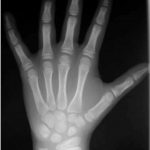

Edad Ósea (Carpo)

El estudio de la edad ósea les permite a los médicos calcular la madurez del sistema esquelético de un niño. Se suele hacer con una radiografía de la muñeca, la mano y los dedos derechos. Se trata de un procedimiento seguro e indoloro en el que se usa una pequeña cantidad de radiación